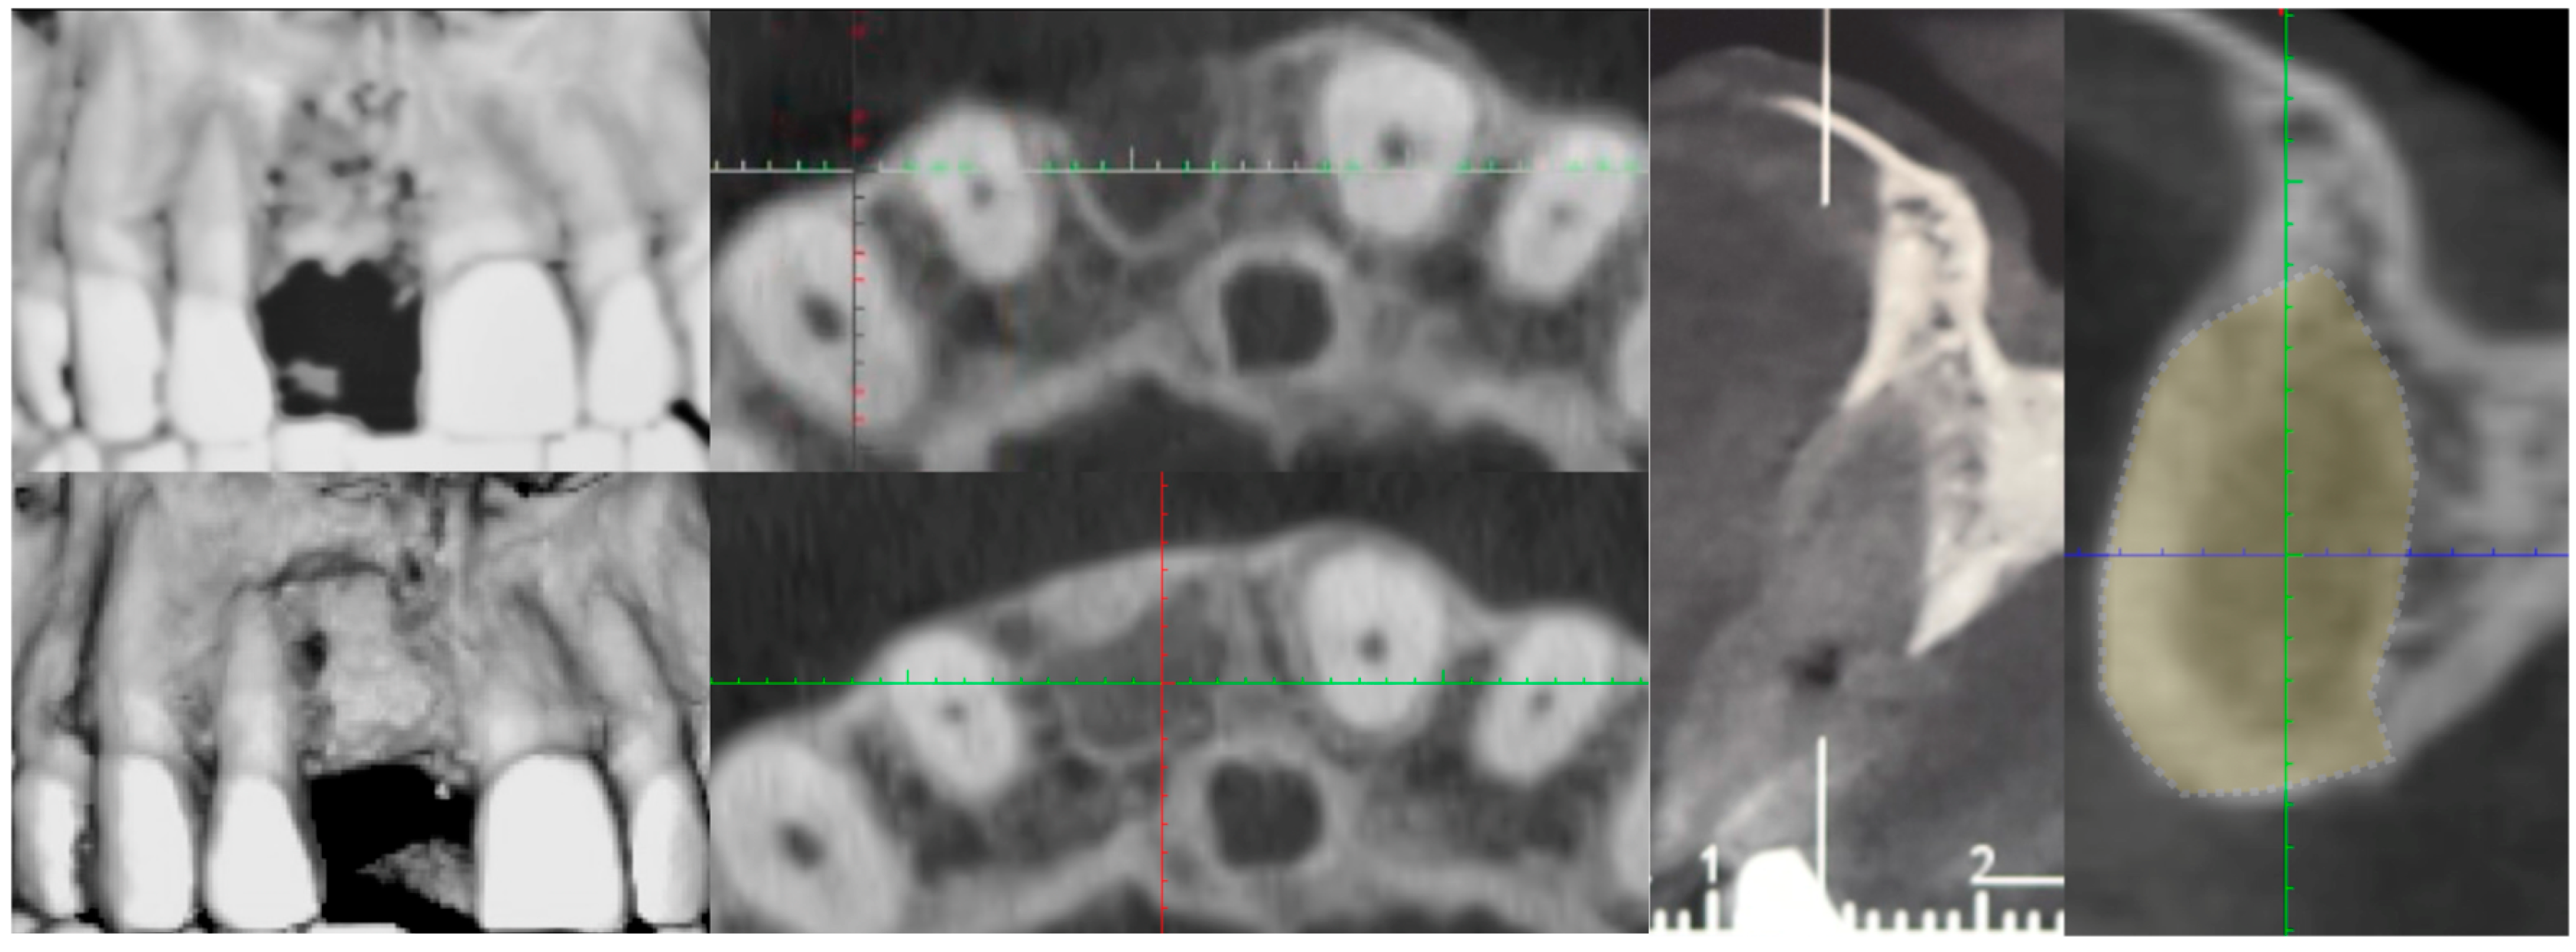

4. Results

Five sites in five patients of ages 26 to 59 with severe ridge deformities were treated with segmented bone lamina. In Table 1 we report the position and extent of the defects. All lesions were measured by CBCT and at surgery with a 15 mm PCP periodontal probe (Figure 17). The thickness of the residual buccal or lingual wall was measured and recorded and as a vertical component the reference point of measurement was the highest bone peak available. After the bone graft and the bone lamina were glued in position the site was re-measured to calculate the augmentation at baseline. Eight months after augmentation the pre-operative CBCT and the follow up CBCT were compared to re-measure the outcome of the procedure (Figure 18). The volumetric changes were evaluated by comparison using Exocad software and on the CBCT on the cross-sections where augmentation was performed (Figure 19 and Figure 20).

In this small sample, four of the residual bone defects had at least one wall of bone available while only one case had both buccal and lingual walls completely missing. In this case the reference point used to assess measurements was the highest bone peak available at the adjacent tooth. The average gain in the horizontal component was 6.18 mm (±1.19 mm), while the average vertical augmentation was 9.70 mm (±2.39 mm).

Figure 18. CBCT Comparison before and after augmentation. In yellow the new volume.

Medicina 61 00683 g018

Figure 19. CBCT comparison, baseline and 8 months after GBR.

Medicina 61 00683 g019

Figure 20. Comparison of CBCT at baseline and 8 months after GBR.

Medicina 61 00683 g020